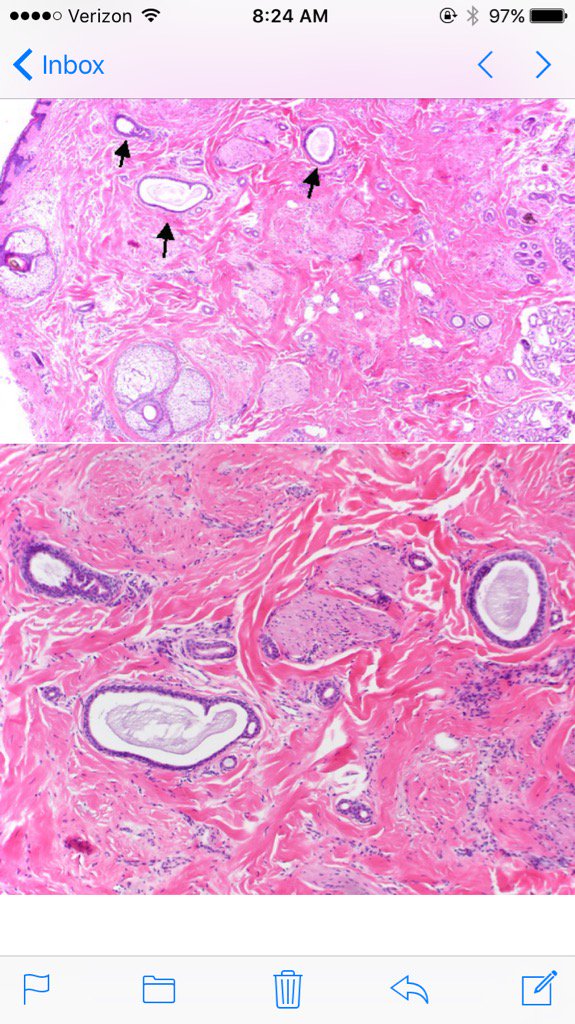

Typical Image of frontal fibrosing alopecia. A few lonely hairs can be seen near the border of the receding hairline #dermpath #asdp2017

LenSperling's tweet image. Typical Image of frontal fibrosing alopecia. A few lonely hairs can be seen near the border of the receding hairline #dermpath #asdp2017